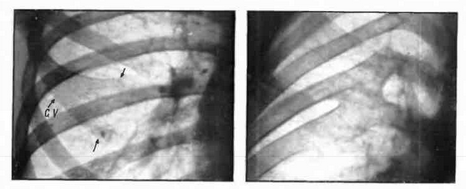

Медицина и диагностика: Аномалии ребер на рентгене